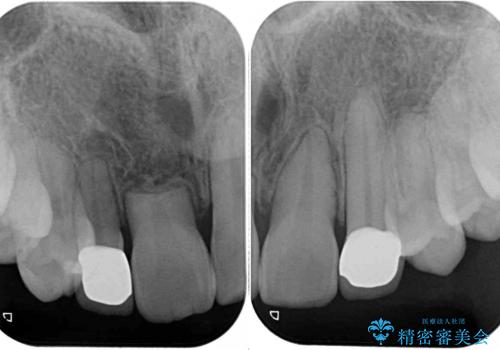

歯根の太さや幅が左右で異なるため、歯肉ラインはどうしても左右非対称となってしまいますが、とても自然な口元となりました。